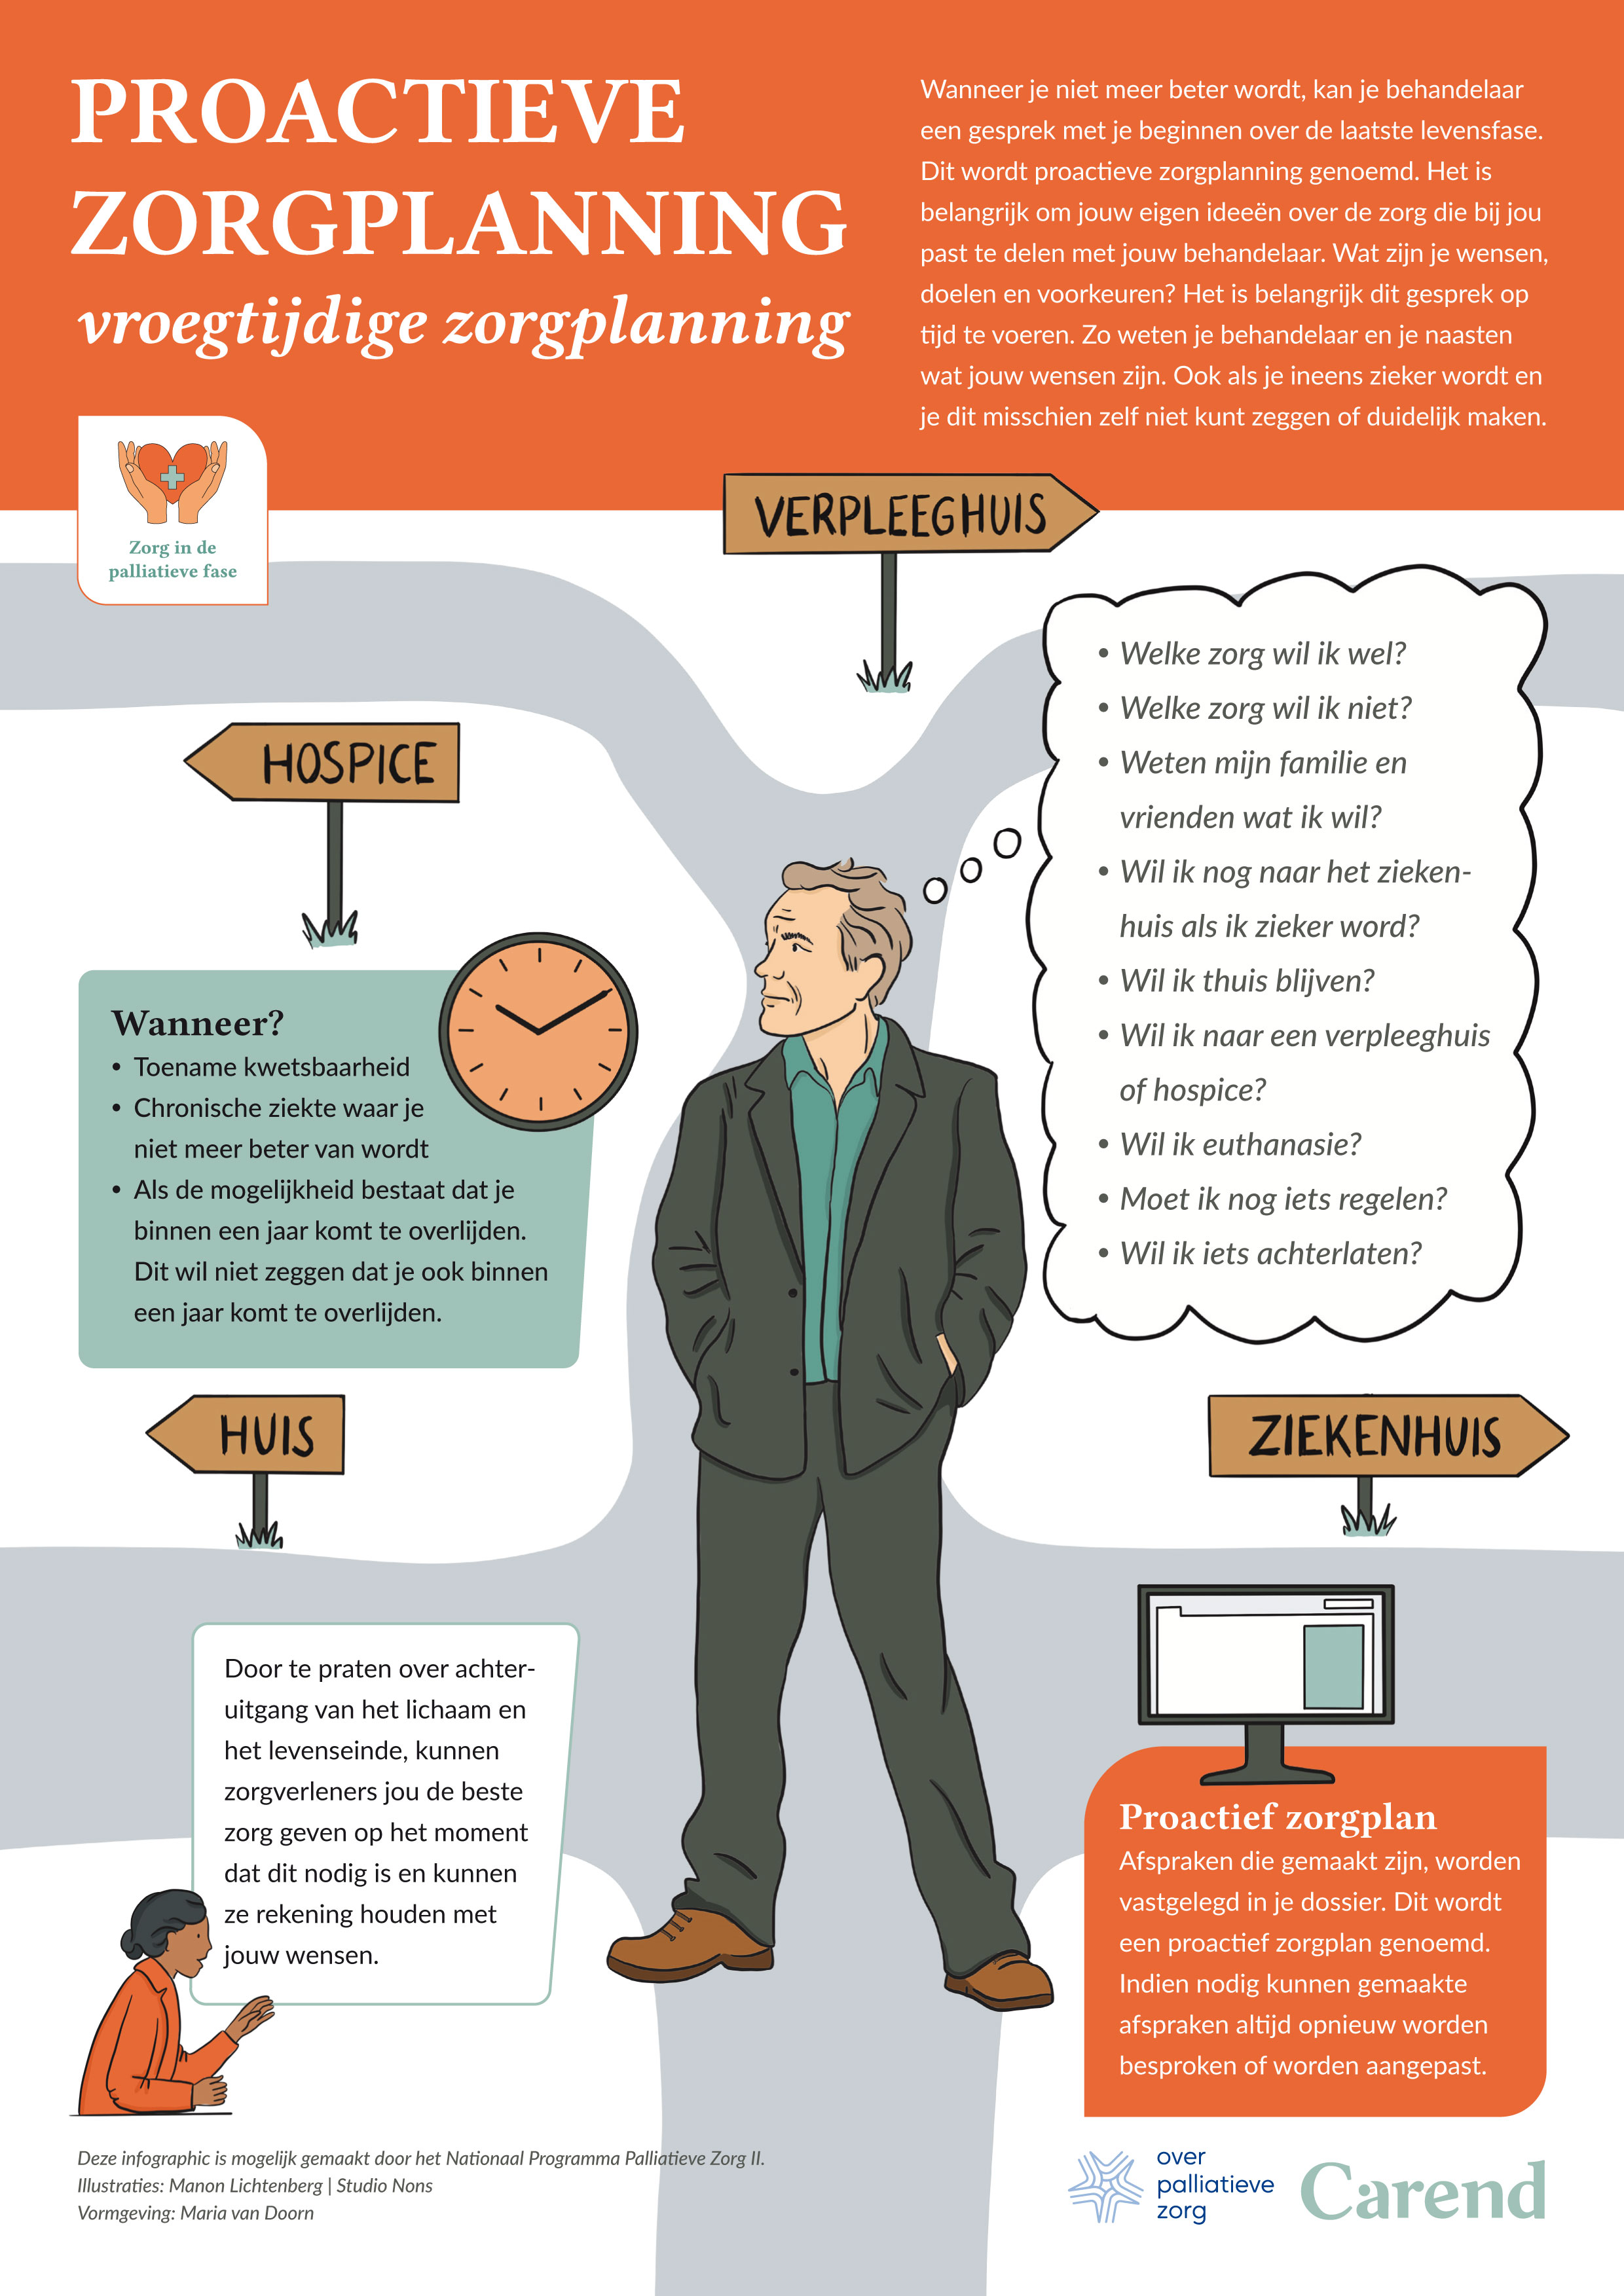

Naarmate de ziekte voortschrijdt, met of zonder dialyse, en de kwaliteit van leven afneemt, worden dezelfde complexe gesprekken opnieuw gevoerd, nu in het kader van proactieve zorgplanning.